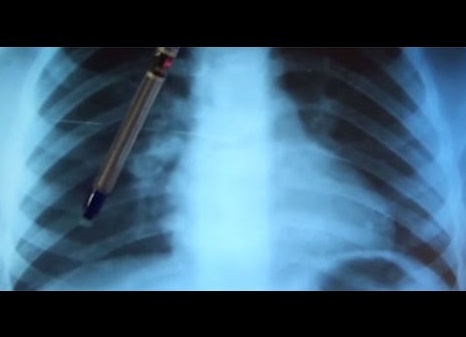

Кальцинаты в легких — «остатки» после туберкулеза, которые представляют собой отложения солей кальция. Они являются защитой для зараженных клеток. Кроме того, причиной их появления могут служить и другие заболевания. В нашем материале мы расскажем, почему они появляются и как проходит лечение.

Кальцинаты представляют собой известковые отложения, нарушающие функциональную способность основных органов дыхания. К примеру, они «крадут» объем легкого, что в результате приводит к нехватке кислорода.

Если есть хоть один из этих факторов, следует обязательно обратиться к врачу. Чтобы выявить основную причину появления таких отложений, назначают проведение компьютерной томографии, изучают реакцию манту, УЗИ.